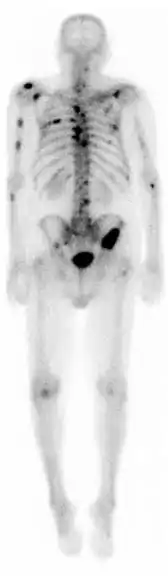

Gammagrafía ósea

Una gammagrafía ósea es una prueba de medicina nuclear para encontrar ciertas anormalidades en los huesos. Se utiliza sobre todo para ayudar a diagnosticar: cáncer de los huesos o cáncer que se ha diseminado (metástasis) hasta el hueso, la localización de algunas fuentes de inflamación en los testículos (por ejemplo, dolor óseo, tales como dolor de espalda debido a una fractura), el diagnóstico de las fracturas que pueden no ser visibles en las tradicionales imágenes de rayos X, y la detección de daños en los huesos debido a ciertas infecciones y otros problemas.

En general, lo que se busca con esta prueba diagnostica son imágenes de hipercaptación que pueden ser localizadas, múltiples o difusas. Cuando son difusas recibe el nombre de superscan. Las imágenes de hipocaptación son más raras. El aumento de captación ósea puede ser por cuatro motivos: el aumento de la formación osteoide, una mineralización ósea aumentada, un aumento de la vascularización, del flujo sanguíneo, o por una denervación simpática.

La técnica en sí consiste en la administración intravenosa de 10-20 milicurios de 99mTc-MDP (Metilén difosfonato) o de 99mTc-HEDP (Hidroxi-Etilén-difosfonato). Tras 2-5 horas postinyección se realiza la adquisición de las imágenes de cuerpo entero, que se llama rastreo anterior y rastreo posterior. Eventualmente, estos rastreos de cuerpo entero se pueden complementar con: gammagrafías localizadas de huesos concretos, SPECT muy útil en columna vertebral y pelvis o gammagrafía ósea de tres fases.